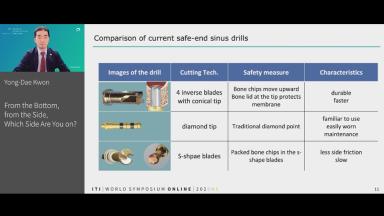

The congress lecture will discuss two techniques for sinus floor elevation (SFE) in implant dentistry: the lateral window technique and the transalveolar technique. Choice of method depends on anatomical considerations such as residual bone. Both methods show high implant survival rates, comparable to native bone (around 95%). Transalveolar SFE is suited for cases with enough residual bone and a flat sinus floor, but risks Schneiderian membrane perforation due to incomplete osteotomy. Advances in surgical instruments, including drills with safety ends and controlled hydraulic pressure, have reduced perforation risks in transalveolar SFE. However, for severely resorbed ridges or the presence of septa, the lateral window technique is preferred. The lecture will cover how to select the appropriate technique for each patient.

- outline how to achieve the controlled erosion of the sinus floor during the transalveolar technique